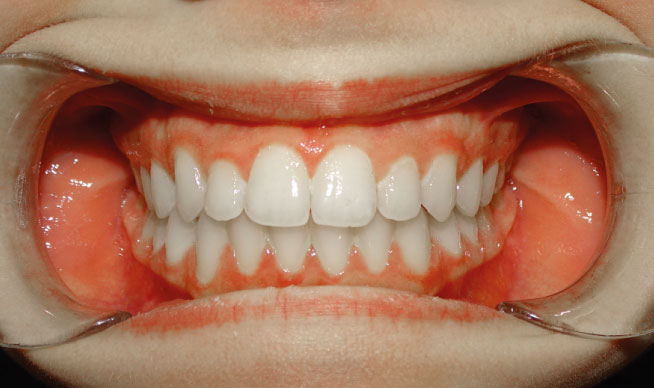

la présence d’une supraclusion, cela signifie que le recouvrement des incisives inférieurs par les incisives supérieures est trop important. Autrement dites, les dents du dessus « cachent » celles du bas, c’est pourquoi on parle aussi de recouvrement dentaire. La supraclusion se manifeste par un recouvrement trop important des incisives inférieurs par les incisives supérieures. Les dents du dessus « cachent »les dents du bas. Ce trouble est fréquent et est aisément traitable grâces aux nouvelles techniques d’orthodontie. Grâce aux nouvelles techniques d’orthodontie, le traitement est facilité́. Il n’est plus nécessaire de porter des « casques » externes et il est très rare d’extraire des dents. Le port de rackets (les « bagues ») permet de résoudre le problème chez l’enfant et l’adulte.